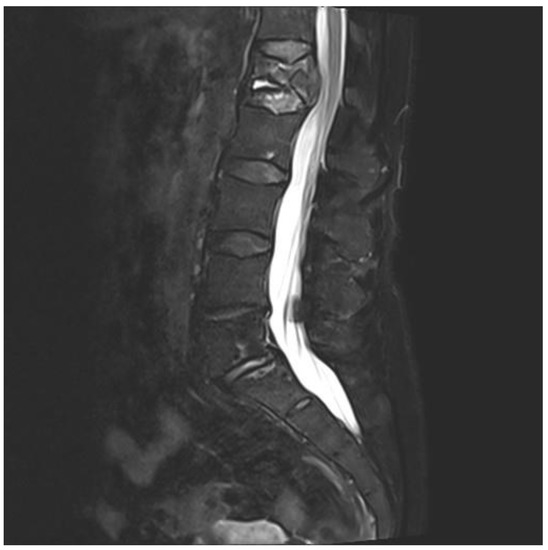

A 75-year-old woman presented with acute pain in the lower back after a trivial incident. Her past medical history included hypertension, hypercholesterolemia, type 2 diabetes mellitus, hypothyroidism, migraine, and arrhythmia. Initial radiological examinations demonstrated no fracture. However, over the next few weeks, her back pain increased. By magnetic resonance imaging (MRI), she was diagnosed with a compression fracture in L1, although with no spinal stenosis (Figure 1). The fracture was initially managed conservatively; however, she had persistent opioid-dependent lower back pain and was admitted to the orthopedic department for further clinical and laboratory diagnostic workup to exclude a pathologic etiology for her fracture.

Figure 1. Magnetic resonance imaging (MRI) of lumbar column. The figure demonstrating collapse and fracture of vertebra corpus L1, with edema and compression against the spinal cord.